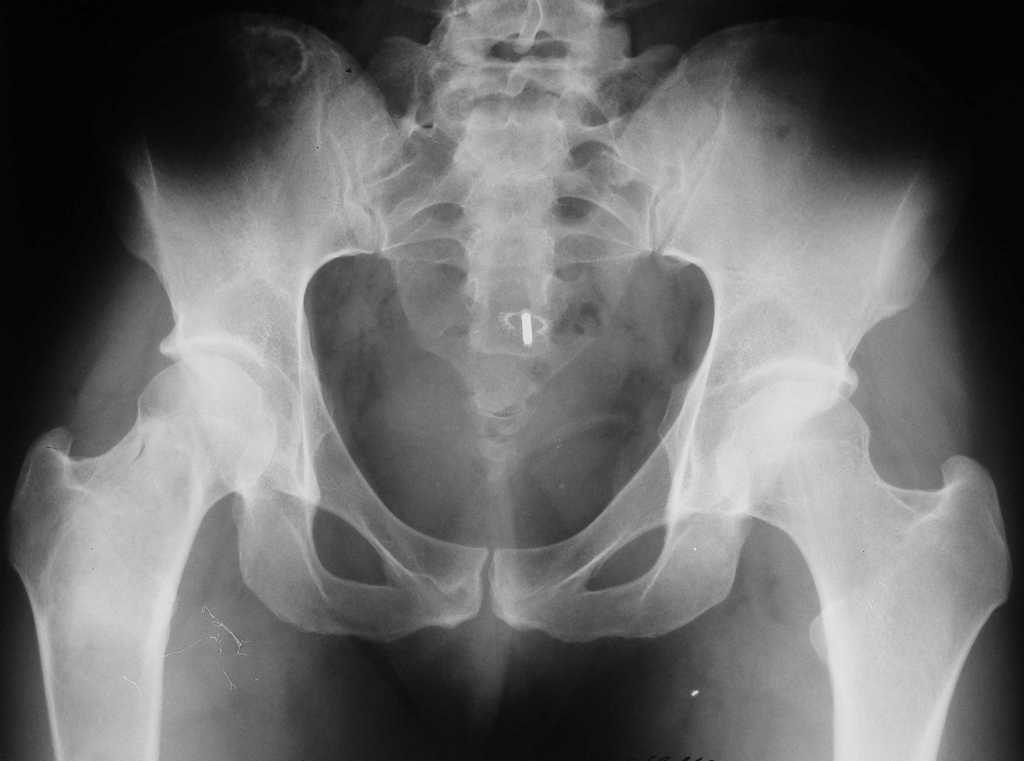

Уважаемые коллеги! В клинику поступила молодая женщина 35 лет с жалобами на интенсивные боли в области правого бедра, носят спонтанный характер, имеются "ночные" боли.

Движения в правом тазобедренном суставе в полном объёме, практически безболезненные. По результатам x-ray диагностики выявлен патологический очаг, занимающий весь проксимальный отдел и 2/3 диафиза правой бедренной кости. Другие трубчатые кости верхних и нижних конечностей - без очагов поражения.

Имеется небольшой (1,5х2,5 см) очаг в крыле правой подвздошной кости.

По результатам трепанобиопсии проксимального отдела правой бедренной кости - фиброзная строма и костные балки, без атипии.